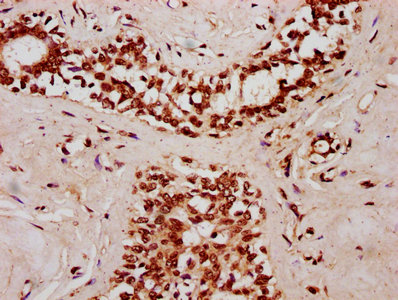

IHC image of CSB-PA854104LA01HU diluted at 1:400 and staining in paraffin-embedded human breast cancer performed on a Leica BondTM system. After dewaxing and hydration, antigen retrieval was mediated by high pressure in a citrate buffer (pH 6.0). Section was blocked with 10% normal goat serum 30min at RT. Then primary antibody (1% BSA) was incubated at 4°C overnight. The primary is detected by a biotinylated secondary antibody and visualized using an HRP conjugated SP system.

IHC image of CSB-PA854104LA01HU diluted at 1:400 and staining in paraffin-embedded human testis tissue performed on a Leica BondTM system. After dewaxing and hydration, antigen retrieval was mediated by high pressure in a citrate buffer (pH 6.0). Section was blocked with 10% normal goat serum 30min at RT. Then primary antibody (1% BSA) was incubated at 4°C overnight. The primary is detected by a biotinylated secondary antibody and visualized using an HRP conjugated SP system.